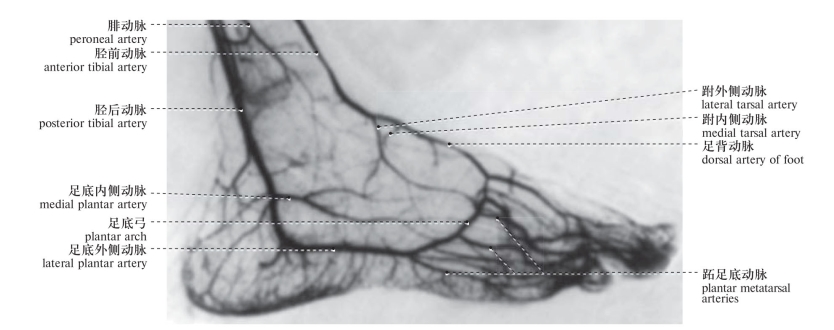

图417 足动脉造影1

Angiography of the foot arteries 1